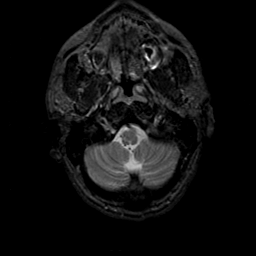

MR Study #23, January 26, 1992 -- Slice #5